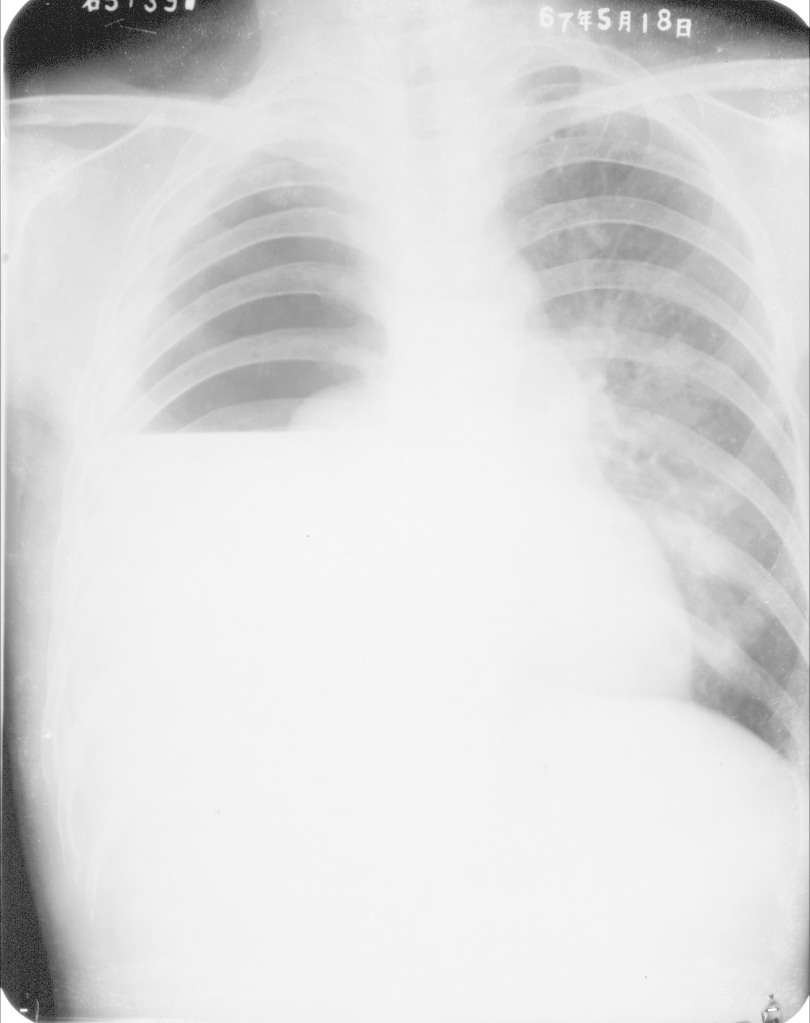

液气胸的X线表现